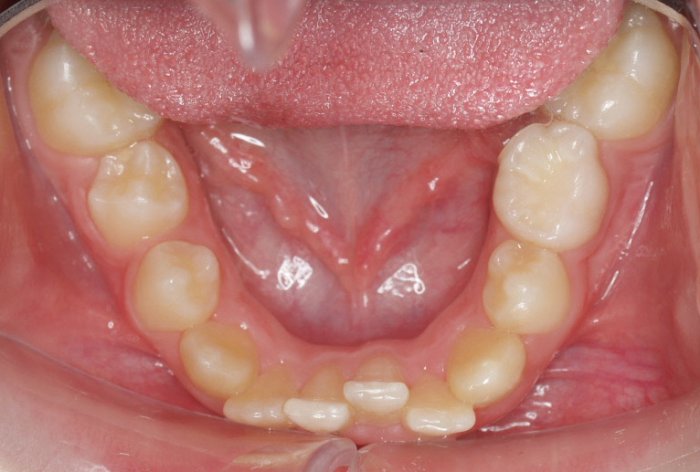

El paciente A.J. de 11 años, acude a nuestra consulta con apiñamiento maxilar importante. El canino lateral (12) está en mordida cruzada. Presenta una Clase II molar y canina, y la línea media está desviada. Se realizó un tratamiento con brackets autoligables metálicos de smartclip 022. La duración del tratamiento fue de 22 meses.

El paciente actualmente ha terminado el tratamiento con brackets y lleva una contención fija de 2-2 en maxilar y 3-3 en mandibular; para complementar también lleva una férula ESSIX durante la noche.

INICIO FINAL